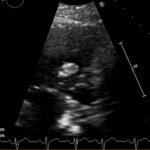

Endovascular coil embolization continues to become a more frequent modality of addressing hemorrhage and bleeding in patients. Migration refers to the coil unraveling or moving from the original embolization site. Migration of a coil is a known complication which can lead to serious consequences based on where the coil migrates. Despite increasing efforts to improve safety and technique, the risk of migration remains. We present a case of an embolization coil that migrated to the right ventricle, which was incidentally found roughly 2 months after undergoing an interventional radiology procedure for gastric variceal bleeding. The patient presented to the emergency department with dyspnea and abdominal pain. Unique images were obtained during his visit and in subsequent follow-up. As use of vascular embolization coils continues to become more commonplace, understanding the risks and complications of these procedures remains an important aspect of providing care for patients once they have left the interventional radiology suite. Coil migration should be a differential to consider in patients who present to the emergency department with signs or symptoms of arrhythmia or pulmonary embolism who have undergone a coil embolization procedure.